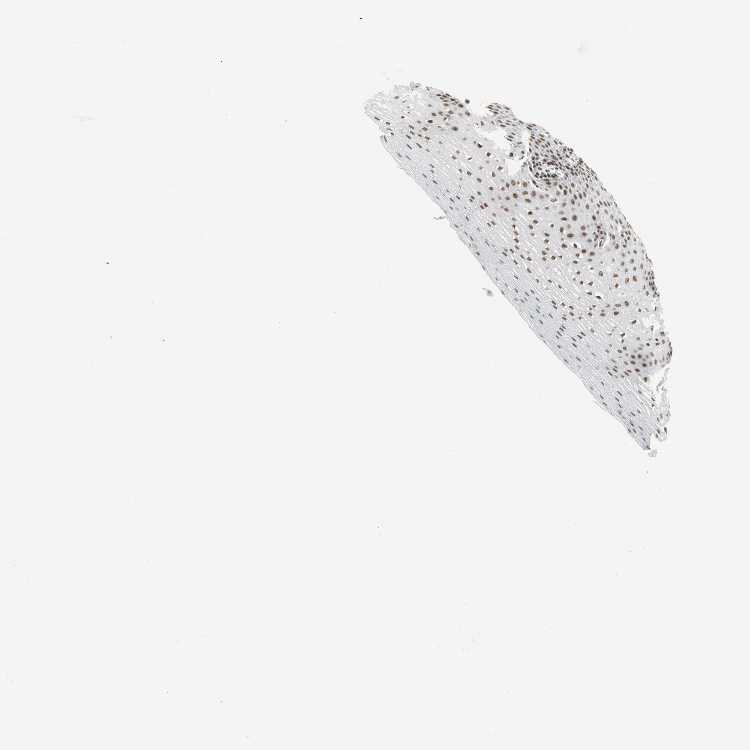

ESOPHAGUS - Antibody stainingi

Antibody staining in the annotated cell types in the current human tissue is reported as not detected, low, medium, or high, based on conventional immunohistochemistry profiling in selected tissues. This score is based on the combination of the staining intensity and fraction of stained cells.

Each image is clickable and will lead to virtual microscopy that enables deeper exploration of all samples and also displays staining intensity scores, fraction scores and subcellular localization as well as patient and tissue information for each sample.

Antibody HPA006714Antibody CAB079946Antibody CAB079947

Squamous epithelial cells HighHighHigh